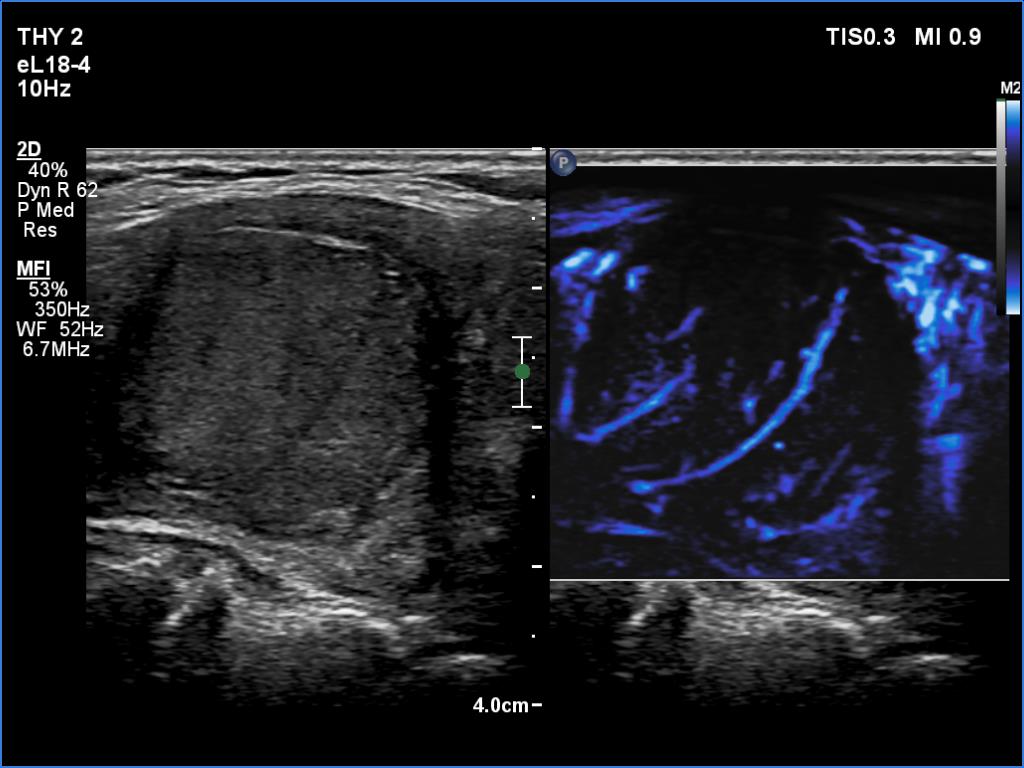

Left lobe, longitudinal view, microflow imaging. The vascular pattern is unusual.